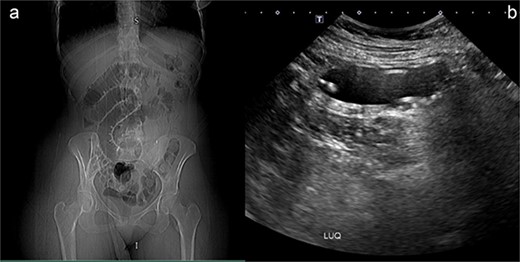

Following the initial evaluations, the patient had an urgent computed tomography (CT) abdominal scan, which revealed that the migrating collapsed gastric balloon, which was trapped in the small bowel loops with proximally dilated loops, was the cause of the small intestinal obstruction (SBO) (Fig. 2). The migrating IGB was determined to be the source of the patient's small intestinal blockage. As the patient was hemodynamically stable and the goal was for the balloon to transit naturally down the alimentary tract, the surgical team advised conservative care at this point.

(a) Coronal view (b) sagittal view (c) axial view of the abdominal CT scan with oral water-soluble contrast showing IGB migrated and impacted in the jejunum with the proximal SBO.